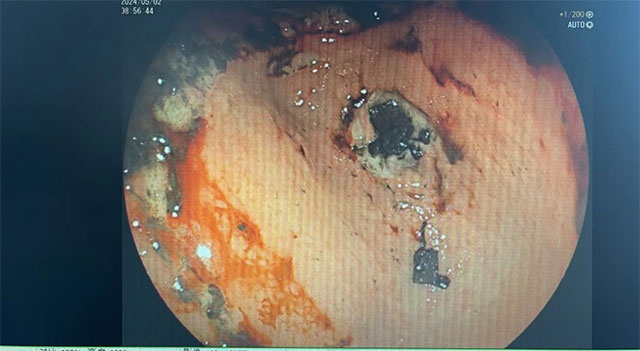

从长期口服头痛粉后,唐大爷开始出现胃疼不适的症状,于是又长期口服胃药,但头痛、胃痛仍时常发作。半月前,唐大爷上腹部疼痛明显加重,难以承受,伴恶心、呕吐、反酸、打嗝,呕吐咖啡色内容物,在河南住院治疗行胃镜提示胃潴留、胃溃疡、幽门梗阻。保守治疗未见好转,于是连夜驱车赶往西南医科大学附属中医医院就诊。

沉积在胃里的内容物

入院时,唐大爷极度消瘦,全身营养状态差,头痛欲裂,口服、注射止痛药均效果不佳,不能进食,进食后隔夜呕吐,医生诊断为“胃窦溃疡伴幽门梗阻”。